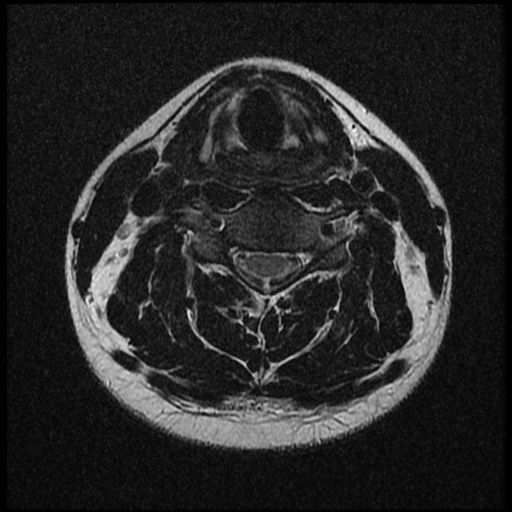

이 MRI 사진은 21년도 사고 당시 찍은 MRI 사진 입니다. 확인 부탁드립니다~

전체 mri를 다 봐여겠지만 보여주신 mri 컷에서는 의미있는 경추 디스크탈출이 보이지 않습니다.